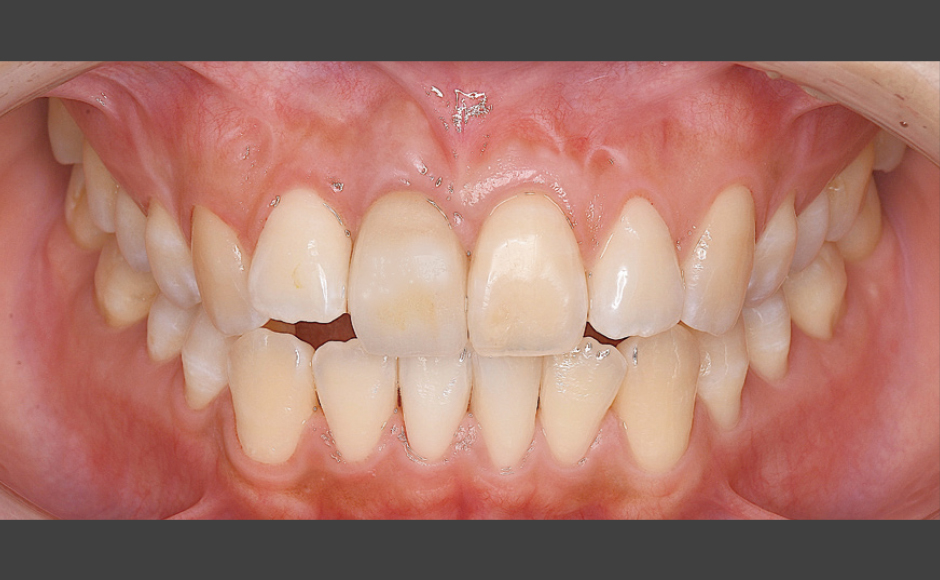

Astratech Implant System EVを使用した審美領域のインプラント治療

症例1:Socket Shield Technique(SST)を用いた審美領域のインプラント治療

症例2:硬軟組織のグラフトを施した審美領域のインプラント治療